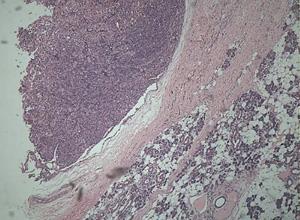

简介嗜酸性腺瘤(oxyphilicadenoma)又称大嗜酸性粒细胞瘤(oncocytom),是一种少见的涎腺良性肿瘤。关于嗜酸性腺瘤的组织发生尚未完全明了,可能来自导管上皮或导管肌上皮细胞。